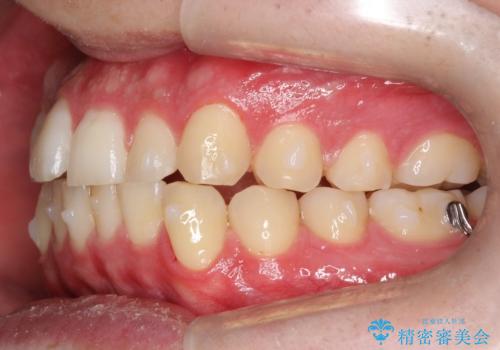

- 前歯の歯並びの改善を希望され来院された患者様です。

初診時の歯並びの状態としては、上下ともに前歯部の中等度以上のがたつき(叢生)があり、右の前歯が1本飛び出した状態でした。

抜歯は行わず上下顎ともに、主に歯列弓の拡大とディスキング(歯と歯の間に隙間を作る処置)を行い叢生を改善しました。